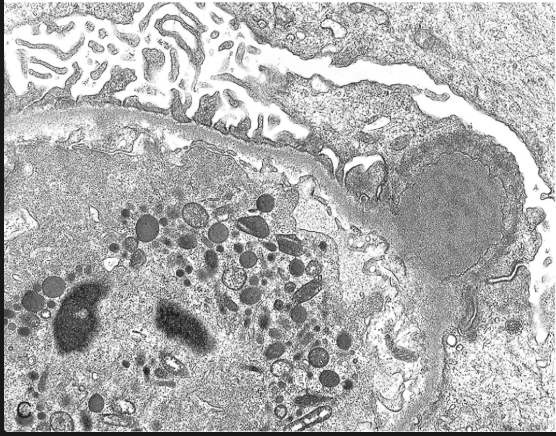

En la microscopía electrónica que es lo que más hace que se distinga de la glomerulopatia infecciosa?

Depósitos definidos, amorfos y electrodensos en la vertiente epitelial de la membrana a modo de JOROBAS